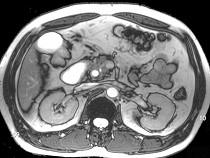

问题 男,43岁,上腹胀痛2个月,频繁呕吐,呕吐物为黄绿色,影像所见如图,可能的诊断为()

选项 A.十二指肠溃疡 B.十二指肠结核 C.十二指肠中分化腺癌 D.十二指肠克罗恩病 E.十二指肠淋巴瘤

答案 C